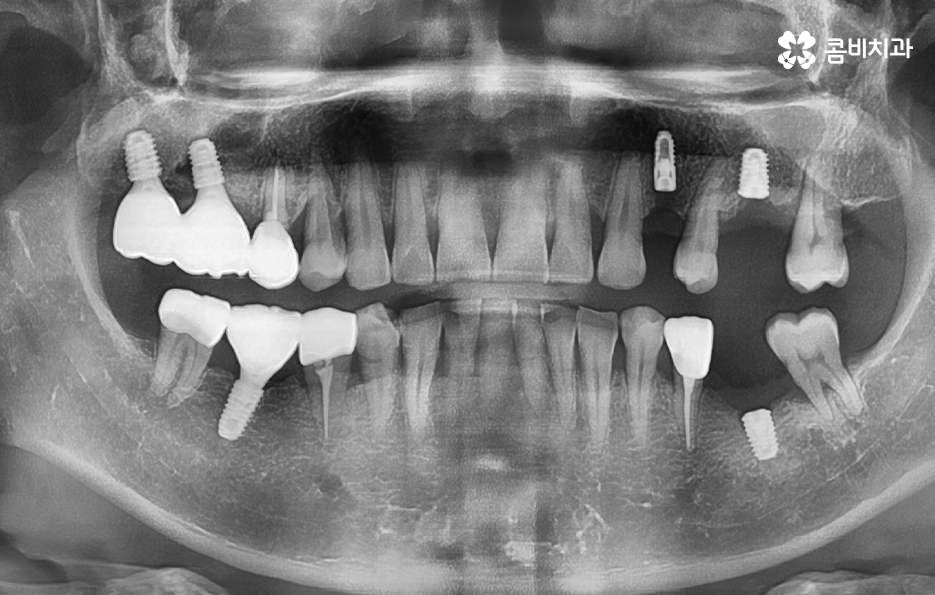

위 케이스의 노인임플란트 치료의 경우 치아의 균열부터 뿌리까지 깊어진 충치, 치주염 까지 복합적인 이유로 치아를 상실하고 여러 개의 임플란트를 식립한 사례라고 할 수 있는데요. 그래도 아직은 잔존하고 있는 치아가 많기 때문에 이미 상실한 치아에는 노인임플란트 각 위치에 맞게 적절한 치료를 받고 나머지의 자연치아에 대해서는 잘 관리하는 것이 중요한 시점이라 할 수 있어요

위 환자분의 케이스는 대부분 어금니 위주로 상실하여 노인임플란트 적절하게 식립하여 어금니의 저작기능을 수복했는데요. 노인임플란트 하면 건강보험에 대한 적용이나 저렴한 치료 비용에 대한 관심을 갖는 경우가 많긴 하지만 연령대에 따라 치아의 잔존율이 크게 급감하는 원인에 대해 잘 알아두시고 이제 치아를 하나 둘씩 잃기 시작했다면 이 시기부터 보다 적극적으로 자연치아를 보존하는 방법을 잘 숙지하시고 특히 주기적으로 치과 검진과 스케일링을 생활화 하는 것이 강조되고 있어요